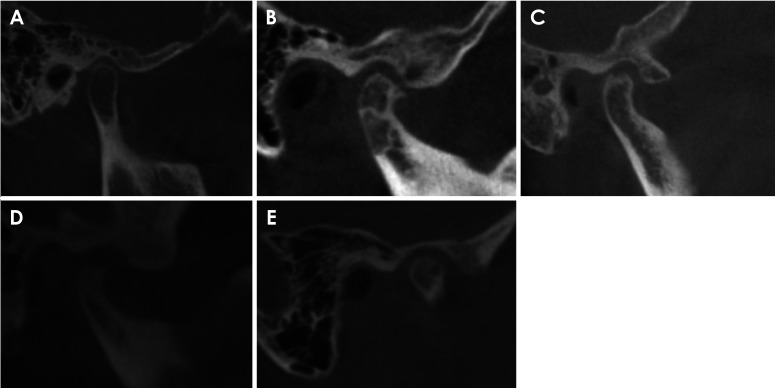

Abstract Image